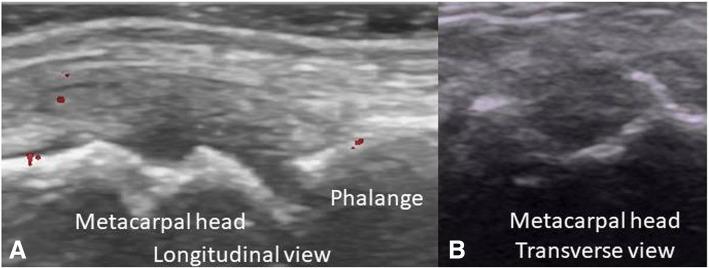

Musculoskeletal Ultrasonography (MSUS) is an important tool for the clinical assessment in Juvenile Idiopathic Arthritis (JIA). The objective of this study was to evaluate the reliability of MSUS to detect elementary lesions: synovitis, tenosynovitis, cartilage damage and bone erosions in the wrist and metacarpal (MCP) joints of patients with JIA.

Thirty children in various subgroups of JIA according to ILAR criteria, were included in this cross-sectional study. Clinical data including painful, swollen and limited joints were recorded. Five rheumatologist ultrasonographers, blinded to the clinical evaluation, evaluated the presence of elementary lesions in the wrist and MCP 2 and 3 joints bilaterally. The synovitis was graded in B-Mode and Power Doppler (PD). In addition to descriptive statistics intra- and inter-observer reliability was calculated using Cohen's kappa according to Landis and Koch.

US detected more synovitis than the clinical examination (62% vs 28%, 30% vs 23% and 22% vs 17% in the wrist, second and third MCP joints respectively). The intra-observer concordance for synovitis in all joints was excellent in B-Mode (k 0.84 .63-1.0 p = 0.001), except for MCP 2, where it was good (0.61, IC 95% .34-89, p = 0.001). For both modalities (PD, B-Mode) tenosynovitis, cartilage damage and bone erosions it was also excellent. Regarding synovitis grading the concordance was excellent for all grades (0.83-1.0, IC 95% 0.51.1.0, p = 0.001), except for grade 1 where it was good (0.61, IC 95% 0.43-.83, p = 0.001). Reliability inter-observer for grayscale synovitis (0.67-0.95, IC 95% 0.67-1.0, p = 0.001), tenosynovitis grayscale (0.89, IC 95% 0.78-0.99, p.001), damage cartilage (0.89, IC 95% 0.78-0.99, p = 0.001), PD (0.66, IC 95% 0.39-1.0, p = 0.001). The concordance for grading synovitis was excellent, but for grayscale grade 1 and 2 (.66, IC 95% .53-.74, p = 0.007) and PD grade 1 and 2 (0.63, IC 95% .58-.91, p = 004) was good.

The intra- and inter-observer reliability of MSUS for inflammatory and structural lesions is good to excellent for the wrist and MCP in patients with JIA.